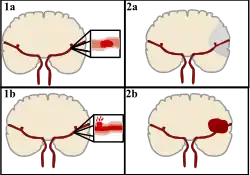

Classification

Stroke can be classified into two major categories: ischemic and hemorrhagic.[20] Ischemic stroke is caused by interruption of the blood supply to the brain, while hemorrhagic stroke results from the rupture of a blood vessel or an abnormal vascular structure.

About 87% of stroke is ischemic, with the rest being hemorrhagic. Bleeding can develop inside areas of ischemia, a condition known as "hemorrhagic transformation." It is unknown how many cases of hemorrhagic stroke actually start as ischemic stroke.[2]

Hemorrhagic

There are two main types of hemorrhagic stroke:[30][31]

- Intracerebral hemorrhage, which is bleeding within the brain itself (when an artery in the brain bursts, flooding the surrounding tissue with blood), due to either intraparenchymal hemorrhage (bleeding within the brain tissue) or intraventricular hemorrhage (bleeding within the brain's ventricular system).

- Subarachnoid hemorrhage, which is bleeding that occurs outside of the brain tissue but still within the skull, and precisely between the arachnoid mater and pia mater (the delicate innermost layer of the three layers of the meninges that surround the brain).